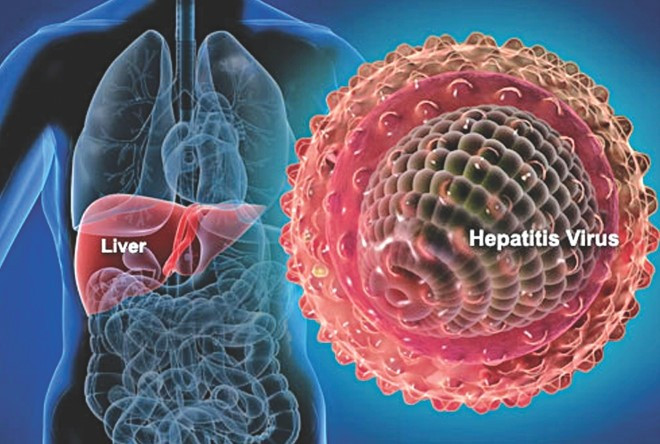

L’infiammazione del fegato può derivare da diverse cause. Oltre alle infezioni da virus dell‘epatite B (HBV) e virus dell’epatite C (HCV), altri virus come il citomegalovirus (CMV) sono in grado di scatenare l’epatite acuta. A volte l’epatite induce la febbre e sintomi simil-influenzali, tuttavia, può anche danneggiare il fegato e potrebbe anche portare a insufficienza epatica acuta. Tuttavia, attualmente non esiste un accordo generale su come l’epatite acuta dovrebbe essere trattata: la risposta immunitaria contro il patogeno virale deve essere rinforzata o inibita? Gli scienziati di TWINCORE hanno ora pubblicato nuove informazioni sui processi coinvolti nell’infiammazione del fegato, nel Journal of Hepatology: Gli interferoni di tipo I, da un lato, limitano la replicazione virale e quindi aiutano le cellule immunitarie a controllare il patogeno virale. D’altra parte, gli interferoni di tipo I ritardano la rigenerazione delle cellule immunitarie che sono importanti per regolare e mantenere l’equilibrio immunitario nel fegato durante l’infiammazione acuta.

“Finora, è stato ipotizzato che la replicazione virale stessa distrugge le cellule del fegato“, dice Katharina Borst, scienziata presso l’Institute for Experimental Infection Research, TWINCORE, Hannover, Germania. “Nel frattempo sappiamo anche che i processi infiammatori locali possono danneggiare il fegato. Questa è una conoscenza critica, perché, se la reazione infiammatoria e non il virus rappresenta un danno epatico, non si dovrebbe aumentare l’infiammazione all’interno dell’organo già infiammato dal trattamento con una citochina infiammatoria come l’interferone di tipo I. D’altra parte, nella pratica clinica è ben noto che l’interferone di tipo I è un trattamento efficace durante l’epatite acuta e che protegge il fegato”, sostiene la Dr.ssa Theresa Frenz, anch’essa scienziata presso l’Institute for Experimental Infection Research, TWINCORE.

Pertanto, gli scienziati hanno cercato di capire il meccanismo con cui l’interferone di tipo I funziona nel fegato. Per comprendere le risposte immunitarie locali, hanno analizzato le cellule di Kupffer, che sono cellule scavenger del fegato all’interno del sistema immunitario.

I ricercatori hanno rilevato che l’interferone di tipo I sembra essere importante per le cellule di Kupffer. Afferma il Dr. Frenz: “Riteniamo che l’interferone di tipo I spinga le cellule di Kupffer a reclutare le cellule infette e a subire l’apoptosi (suicidio). Dopo l’infezione infatti, le cellule di Kupffer scompaiono. Il corpo sostituisce quelle cellule Kupffer perse con le cellule scavenger che si sviluppano dal midollo osseo. Tali cellule non sono “reali” cellule Kupffer, ma assumono comunque compiti simili. ” È interessante notare che questo processo è accelerato se le cellule del midollo osseo non sono in grado di rilevare l’interferone di tipo I “, afferma la Dr.ssa Borst.” Ovviamente, l’interferone di tipo I è molto importante per la regolazione dei processi infiammatori”.

“Abbiamo verificato che il trattamento terapeutico dell’epatite virale acuta con interferone di tipo I è ragionevole, dal momento che attiva le cellule immunitarie locali e aiuta a eliminare il virus”, conclude il Direttore dell’Istituto Prof. Ulrich Kalinke. “Tuttavia, al fine di sostenere meglio la rigenerazione del fegato infiammato, abbiamo bisogno di saperne di più sull’equilibrio di potenziamento e modulazione dell’infiammazione che sarà la base per sviluppare nuovi interventi terapeutici per l’epatite acuta”.